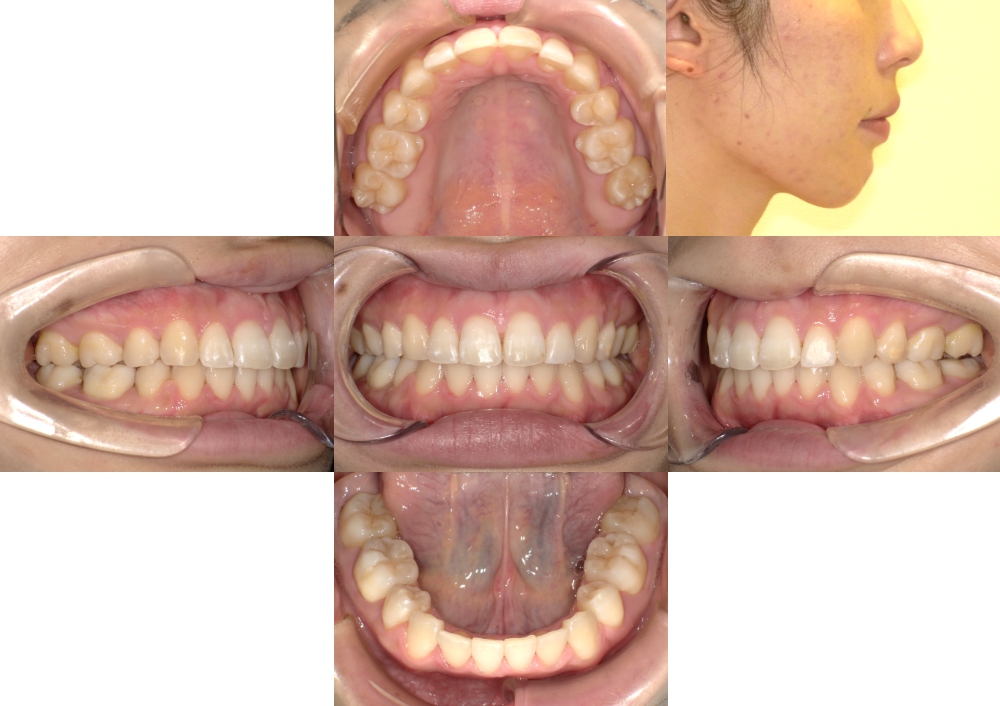

症例3

上顎前突、叢生

抜歯

ブラケット矯正

(初診時)年齢

25歳

性別

女性

地域(住所)

府中市

主訴

デコボコ、出っ歯

診断

叢生を伴う上下顎前突

装置

マルチブラケット装置

上顎口蓋に歯科矯正用アンカースクリューを併用

抜歯/非抜歯

上顎両側5番、下顎両側4番、上顎左側7番抜歯(計5本)

期間

2年3か月

費用

840,000円(税抜)(矯正装置・保定装置代込)

調整料 5,000円(税抜)×35回

症例写真

BEFORE

AFTER